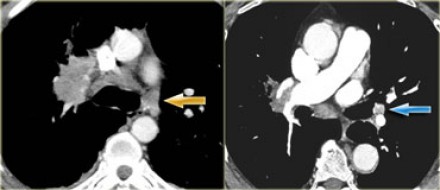

N1-стадия

N2 - стадия На данном снимке N2-стадия у пациента с ипсилатеральной медиастинальной

или субкаринной лимфаденопатией. |

N3 - стадия При N3-стадии визуализируют контралатеральную медиастинальную или контралатеральной хиларную лимфаденопатию или лимфааденопатию надключичных узлов. Считается нерезектабельным состоянием. |

N3-стадия При N3-стадии визуализируют контралатеральную медиастинальную или контралатеральной хиларную лимфаденопатию или лимфааденопатию надключичных узлов. Считается нерезектабельным состоянием. |

N-стадия правое легкое

|

N-стадия левое легкое